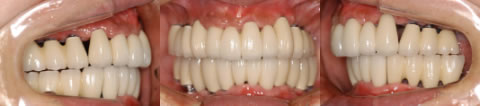

患者さんは48歳(女性)。全顎に義歯が装着されていましたが動かなくて、よく咬めるインプラント治療を希望の為来院。

写真5〜8はそれぞれ術前・後の左側口腔内写真とパノラマレントゲン画像です。

全顎にインプラントブリッジが装着され、審美的にセラミックで回復を施し、美しい笑顔が獲得された。さらに咀嚼機能も改善され患者さんも満足した症例である。

術後のパノラマレントゲン写真では、上顎10本、下顎8本のインプラントが埋入されている事が確認できる。